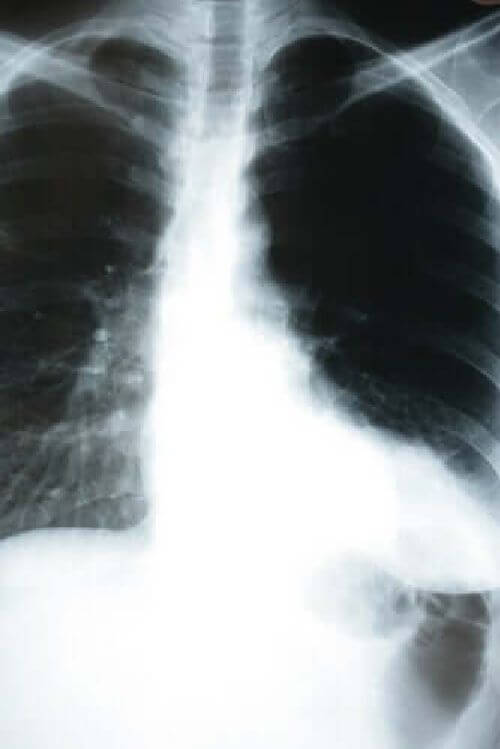

Bezobjawowe zapalenie płuc jest zwykle wykrywane przez pomiar nasycenia krwi tlenem lub przez prześwietlenie klatki piersiowej. Jest to jedno z możliwych powikłań wynikających z infekcji wirusem SARS-CoV-2.

Jednak postawienie takiej diagnozy wymagało najpierw przeprowadzenia pomiaru poziomu tlenu we krwi lub prześwietlenia klatki piersiowej.

Tak więc, jeśli podejrzewasz, że masz koronawirusa, zalecamy lekarzom zmierzenie poziomu nasycenia krwi tlenem. A nawet prześwietlenie klatki piersiowej. Jest to szczególnie ważne, jeśli miałeś kontakt z osobą zarażoną lub przebywałeś w rejonie o wysokim wskaźniku infekcji.